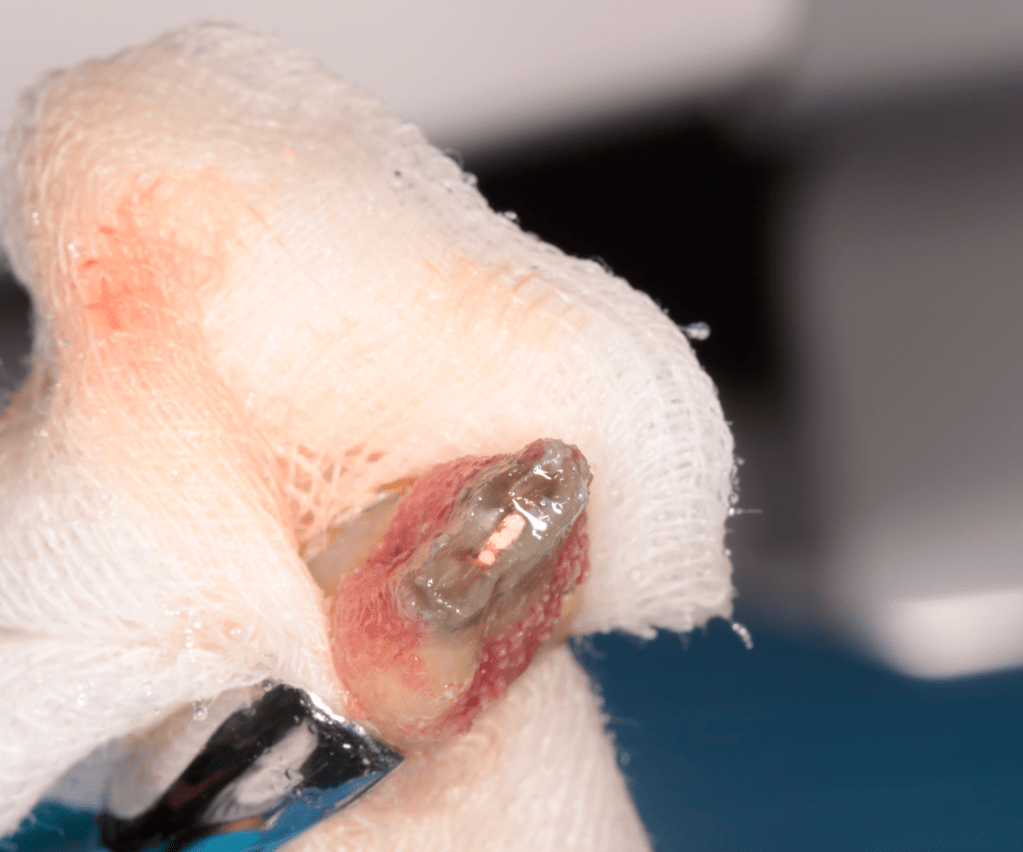

Autotansplantes

REIMPLANTES

Intencional por dificil acceso coronal y quirúrgico

Reinplante por fracaso de tratamiento

Reimplante, istmo apical, curación cortical palatina 1 año